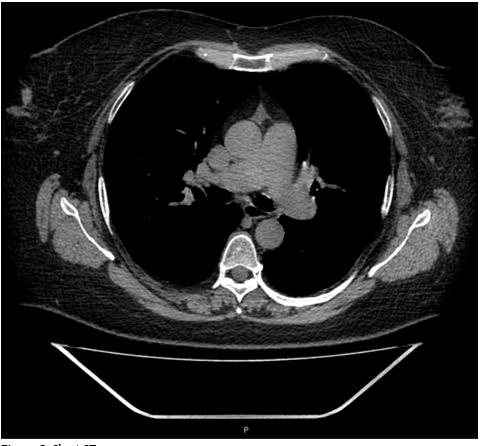

Chest CT findings showed diffuse air trapping without infiltrates nor interlobar and septal thickening; demonstrated absence of pneumonia (Figure 2) and pulmonary hypertension (Figure 3) with length of pulmonary artery of 33.2 mm (secondary to her COPD diagnosis). She received ambulatory management after symptoms onset with oral dexamethasone 6 mg daily per ten days, oral baricitinib 4 mg daily per 14 days, and supplementary oxygen (FiO2 45%) for 15 days. Pulmonologist decided to continue medical management at home due to her stable general conditions. Her SaO2 did not decrease further, her X-ray did not show any further changes (such as pneumonia) and her laboratories did not show clinically significant alterations, especially in regard to inflammation biomarkers. After 15 days of follow-up, dyspnea decreased (mMRC=1), and the SaO2 with FIO2 25%, was over 92%, her evolution was favorable, and she accepted to maintain using oxygen according to her previous condition.

This case shows two different but very relevant issues. First of all, the possibility of developing COVID-19 despite an active vaccine and secondly, its efficiency to prevent severe outcomes in a fragile woman with severe COPD. She received two doses of the sputnik vaccine on time, although the symptoms onset appeared 10 days after receiving the last dose, the immunity achieved was enough to avoid hospital admission. Data of the phase III interim report of Sputnik V showed that about one quarter of those who entered the trail had comorbidities, a known risk for COVID-19 severity. A time-resolved plot of the incidence rate showed that the immunity required to prevent disease arose within 18 days of the first dose. In all age groups, the anecdotal case histories of those vaccinated but infected suggest that the severity of disease decreases as immunity develops [11]. The vaccine that was applied to the patient is characterized for having recombinant adenovirus as vaccine vectors and being able to provide immunity after just a single dose [10]. Nevertheless, she received two doses, the period time between the last one and the symptoms onset were not enough to avoid the infection. However, the first dose she received was sufficient to achieve immunity to prevent a severe infection demonstrated by her clinical picture, chest x-ray, chest CT, SaO2 and lack of increased inflammatory markers (CRP, ferritin, VSG).